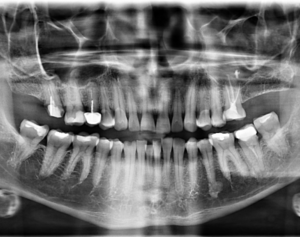

Por lo cual se diseñó un estudio transversal con 74 contactos de 28 imágenes CBCT existentes de niños de entre 3 y 14 años, obtenidos de la Academia de Educación Dental de la India, Chennai, India. La forma del área de contacto se observó en tres niveles, los tercios coronal, medio y apical, en tres secciones diferentes de CBCT. La prevalencia de los tipos de áreas de contacto se expresó en forma de números y porcentajes. Los resultados mostraron cuatro tipos diferentes de áreas de contacto entre los molares primarios, a saber, tipo O, tipo X, tipo I y tipo S, según las formas observadas; Por lo tanto, la clasificación propuesta se conoce como OXIS. El patrón más común observado fue I (66.2%), seguido de X (21.6%), O (9.4%) y el menos común fue S (2.7%). (Figura 1 y Figura 2)

Llegando a la conclusión que la evaluación tridimensional de las áreas intactas de contacto interproximal entre los molares primarios es de cuatro tipos, O, X, I y S.